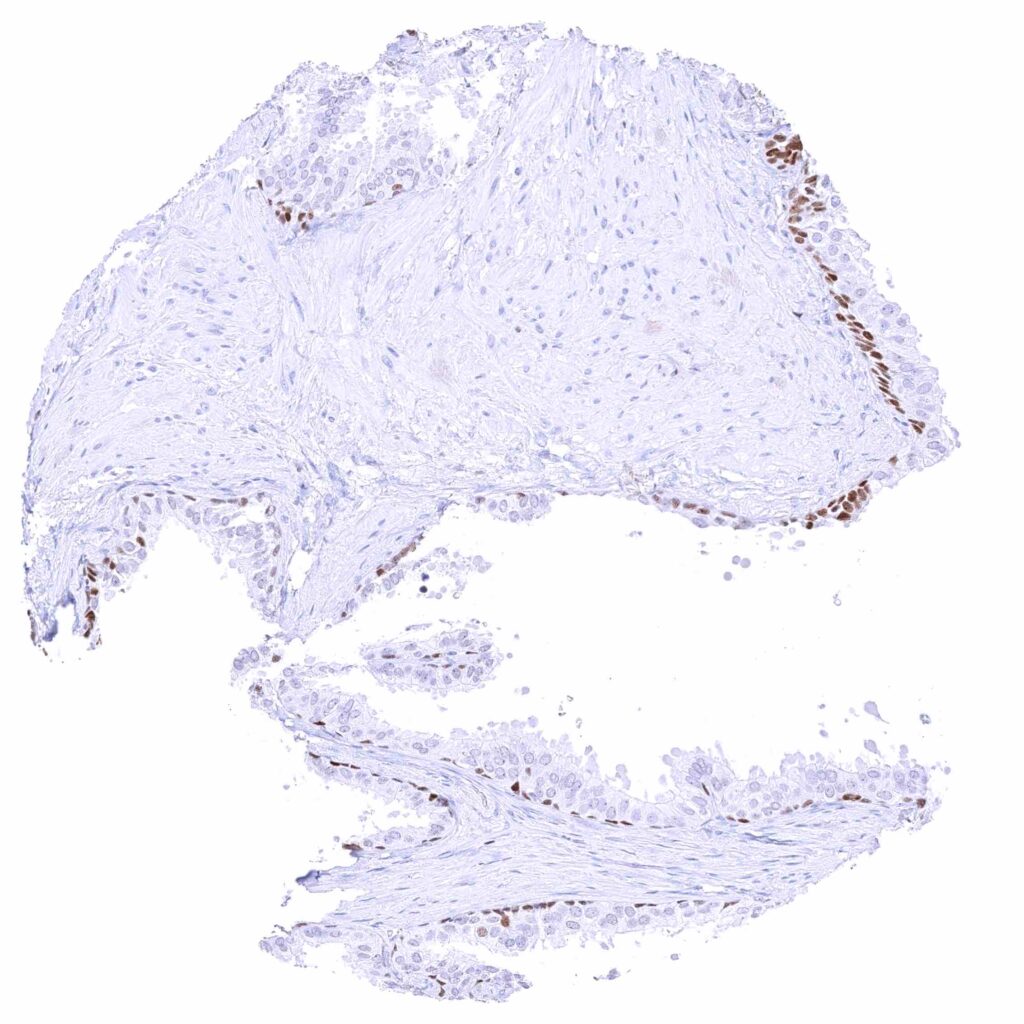

Uterus, ectocervix – Weak to moderate nuclear GATA3 staining of squamous epithelial cells.